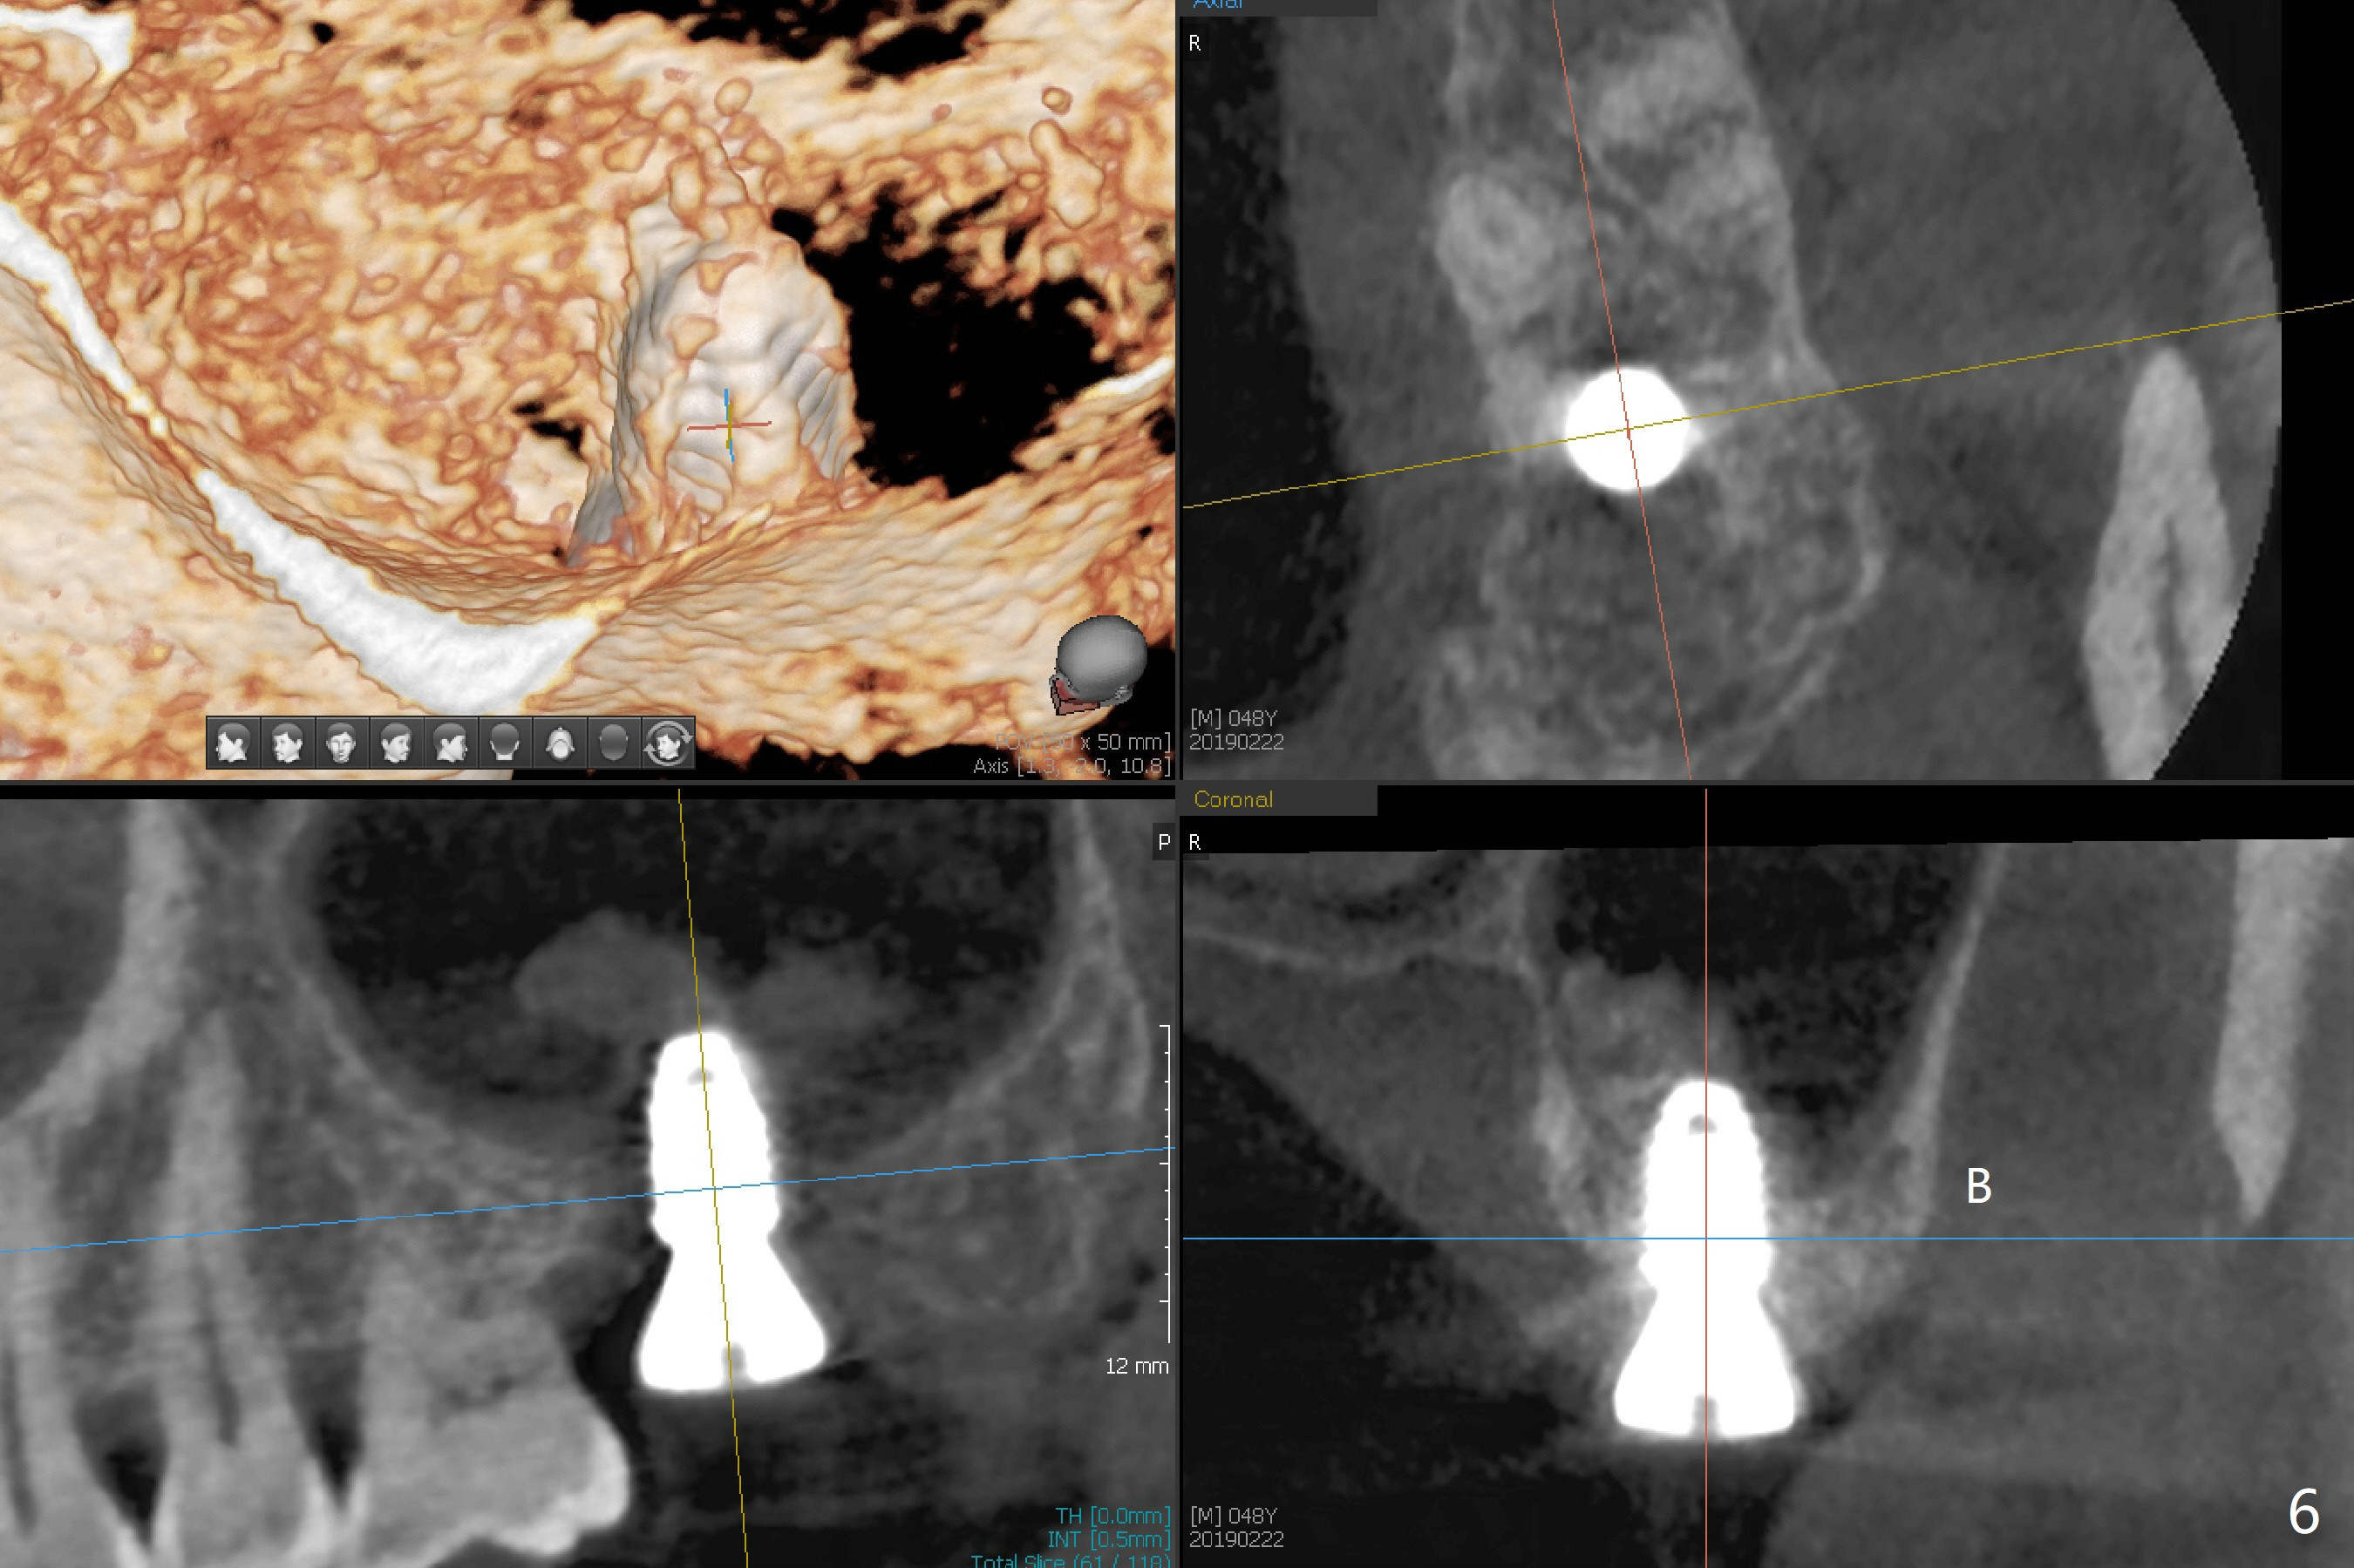

After 4.5x7.3 mm drill with 3 O-rings at #15, use 2.2x7.3 mm one with 2 O-rings. The sinus floor feels like to be perforated, but perio probe does not find the perforation. Nose blowing does not reveal air leakage. It seems fine when 3.0x7.3 mm one with 2 O-rings is being used. The sinus membrane perforates when Magic Sinus Lifter is used. Mixture of autogenous bone (from drills) and allograft does not stick to the periosteal elevator (Fig.1). Forty-minute centrifuge leads to separation of serum (Fig.2 S) from Red Blood Cell layer (R). The separation of the top tube is incomplete with RBC invade the serum layer in a few second (Fig.3 arrow). While the serum layer of the bottom tube is prepared for PRF membrane, a part of the serum layer of the top tube is withdrawn to make sticky bone (Fig.4). The top tube returns to the centrifuge for another 30 minutes to make the second PRF membrane. The first PRF membrane is inserted into the osteotomy and pushed into the sinus with empty feeling, followed by the sticky bone and last by the 2nd PRF membrane. A 5x7.3 mm implant is placed with ~ 10 Ncm, followed by a 6.8x4 mm healing abutment (Fig.5,6 (retrospectively healing screw should be used to reduce sinus-oral communication)). There is no mushroom in the sinus, but hopefully the sticky bone will stick to the bottom of the sinus for maturation. Sinus surgery precaution is provided. Next time tap or dummy implant will be used for sinus lift after initial osteotomy with guide. In fact the patient with diabetes under control has mild cold. The procedure should have been canceled. There is no postop nasal hemorrhage or discharge. The patient returns nearly 8 months postop. The wound is infected. The healing abutment is changed to a healing screw with oral antibiotic. Two weeks later, the area remains infected with symptoms (Fig.7-9). The healing screw is not covered completely. After implant removal, the sinus membrane is perforated. A piece of collagen plug (preferably Osteogen plug) is inserted (Fig.10,11). Because of the concavity, bone graft seems necessary when the wound heals. One week later, perimplantitis develops at #2. The patient is ready for the 3rd placement 1 year 5 months post last implant removal (Fig.12). The bone is 1.8 mm thick, apparently composing of 2 fused cortical plates. Make an incision for both external and internal sinus lift with retraction. Find the old guide to start osteotomy including bone trimmers and use Magic Lifter. If the membrane is broken, open the lateral window to repair with PRF.